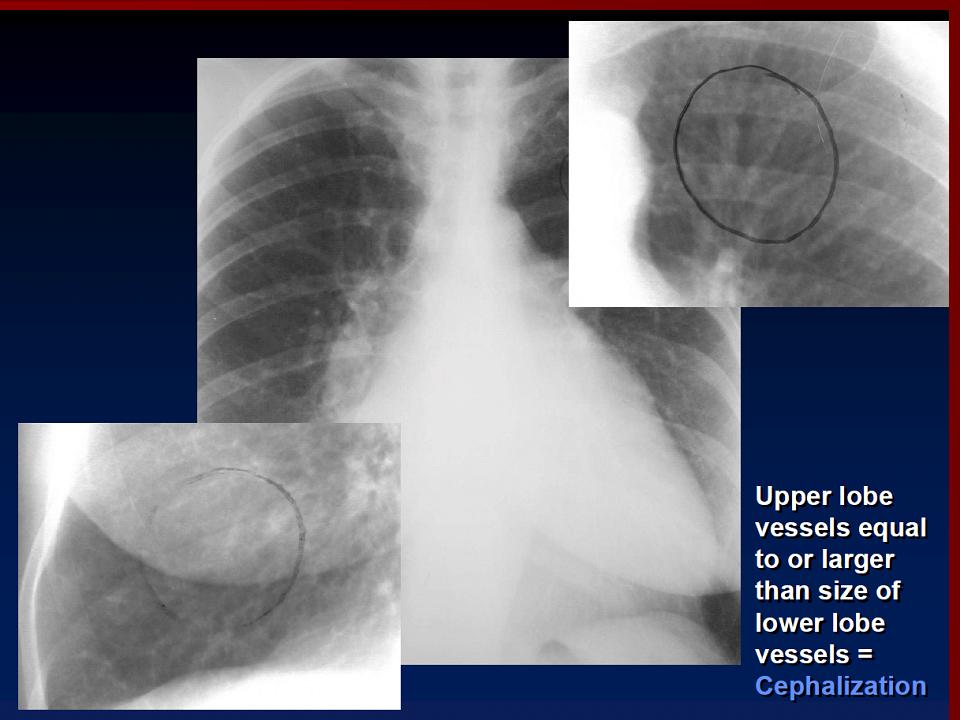

На ЭКГ выявляют митральную форму зубца Р (гипертрофия левого предсердия), признаки гипертрофии правого желудочка, позднее — мерцательную тахисистолию. На ФКГ регистрируются диастолический шум с пресистоличе- ским усилением, высокая амплитуда I тона, щелчок открытия митрального клапана, удлинение интервала Q — I тон от 0,08 до 0,1 с. На эхокардиограмме (М- сканирование) выявляют П-образную форму клапана. При рентгенологическом исследовании обнаруживают сердце митральной конфигурации — (сглаженность талии за счет выбухания дуг левого предсердия и легочной артерии), усиление сосудистого рисунка (линии Керли), отклонение контрастированного пищевода по дуге малого радиуса. В части случаев точная инвазивная диагностика порока достигается путем пункции левого предсердия, позволяющей выявить увеличенный предсердно- желудочковый диастолический градиент. Ценную информацию дают катетеризация сердца и рентгеноконтрастное исследование.

Линии Керли.